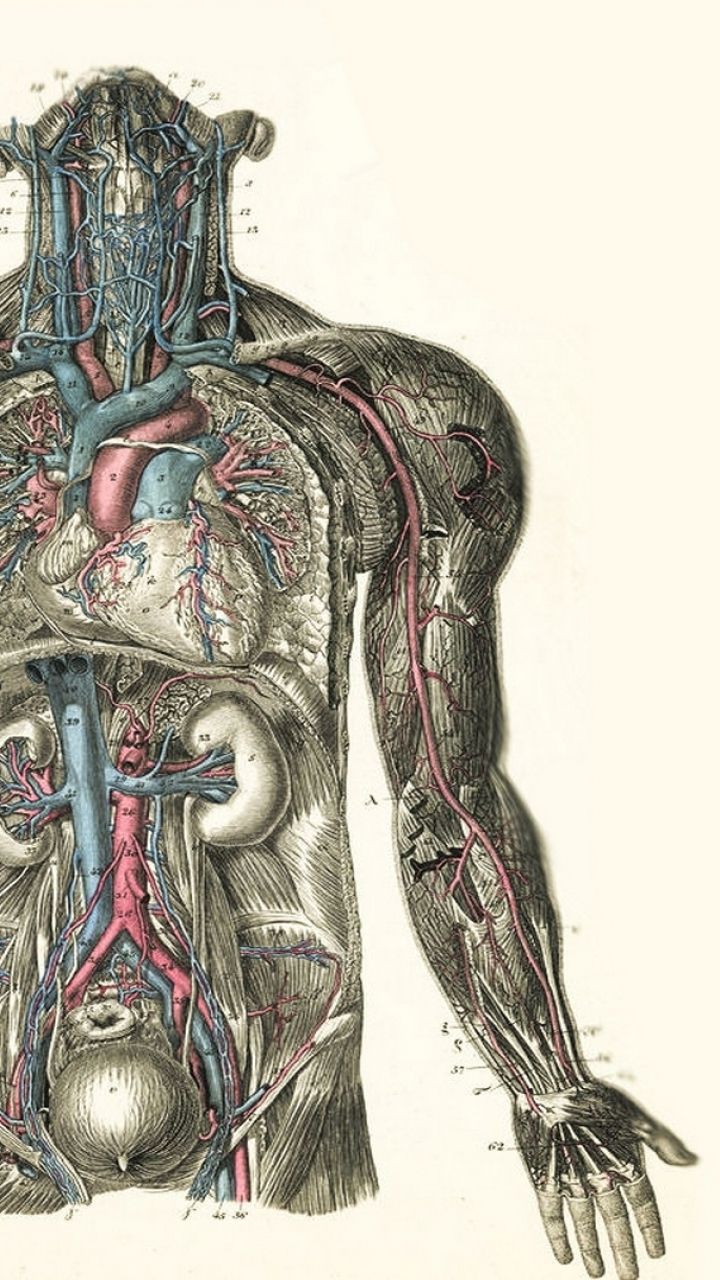

www.ebth.comAnatomy Background, Vintage Anatomy HD Wallpaper | Pxfuel

www.ebth.comAnatomy Background, Vintage Anatomy HD Wallpaper | Pxfuel

www.pxfuel.comAnatomía Vintage Imprimir Mostrando Un Diagrama De Estructuras En Y

www.pxfuel.comAnatomía Vintage Imprimir Mostrando Un Diagrama De Estructuras En Y